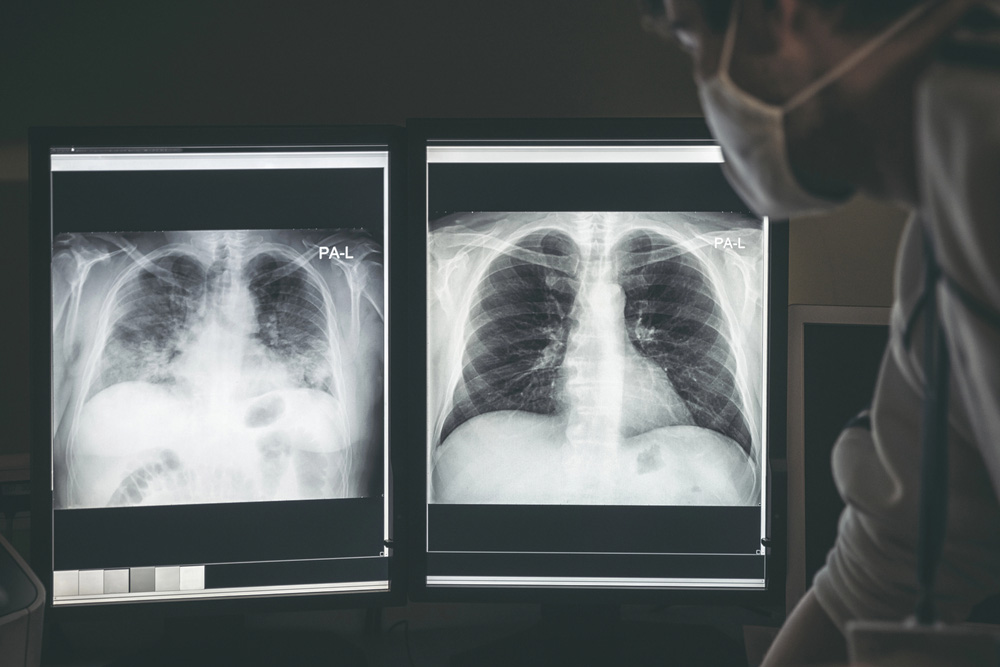

Medical imaging is a critical tool for diagnosing injuries and illnesses, and X-rays remain one of the most widely used imaging methods. While X-rays are highly effective for viewing bones and dense structures, many people wonder how well they can detect soft tissue problems.

X-rays are a form of electromagnetic radiation that can pass through the body. Dense structures like bones absorb more X-rays and appear white on the image, whereas less dense structures, such as muscles, fat, and organs, allow more X-rays to pass through and appear darker. This density contrast helps radiologists distinguish different parts of the body.

How Radiologists Interpret X-Rays for Soft Tissue Problems

Even though X-rays are not perfect for soft tissue imaging, skilled radiologists can detect subtle signs that suggest a problem. Interpretation often involves looking for:

- Changes in soft tissue shadows indicating swelling or mass

- Displacement of bones suggesting ligament or tendon injury

- Calcifications in soft tissue that may signal chronic injury or disease

Radiologists combine X-ray findings with the patient’s symptoms and medical history to provide a more accurate assessment.